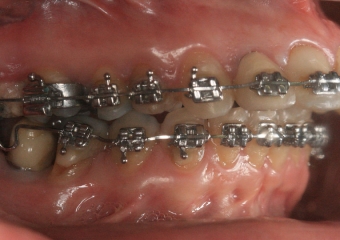

Mordida perfil inicial